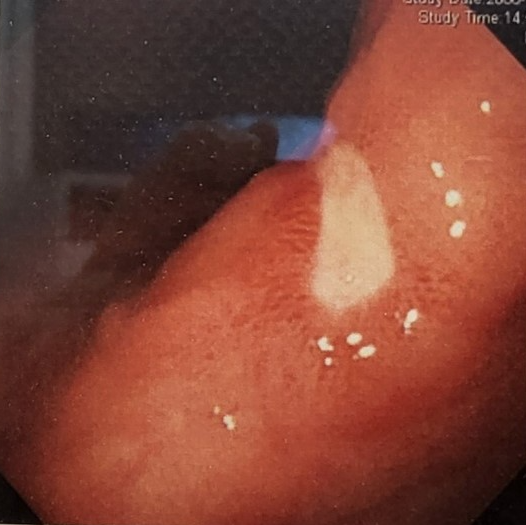

헬리코박터위염